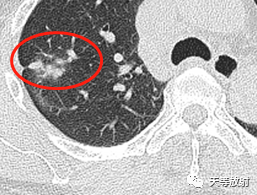

18d907124326f11affdbc1d6e92eed95.png

实性结节呈分叶状改变,邻近胸膜增厚,有牵拉改变,凹陷征。

囊腔壁厚薄不一。

囊腔周围见长条索状影,代表组织受到牵拉聚拢。此时病例的影像学特点:

病变发生于右肺上叶;

实性结节+囊腔

实性略呈分叶状,周围见长条索状影;局部收缩,胸膜凹陷;

囊腔壁厚薄不一。这个结节表现出一定的恶性征象:分叶状实性结节,胸膜凹陷及血管聚拢改变。